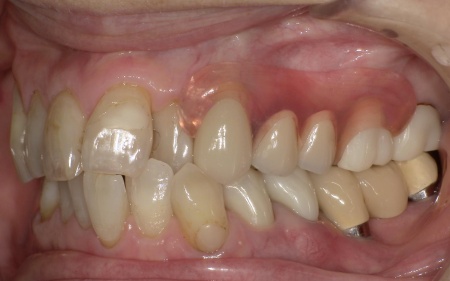

今回は審美性を考慮して、金属のバネではなく樹脂の留め具で固定する部分入れ歯「ノンクラスプデンチャー」を提案し、同意いただきました。

ノンクラスプデンチャーの留め具は歯茎に近い色をしているため、目立ちにくいのが特徴です。

また、体調が回復した時点でインプラント治療へ移行する可能性もふまえ、ノンクラスプデンチャーは手術部位を圧迫しにくく、調整がしやすい設計で作製することになりました。

3ヶ月間の経過観察後、傷が治癒したことが確認できたため、ノンクラスプデンチャーを作製するための型取りを行いました。

また、噛み合わせの記録を取ったり、周囲の歯に馴染む色調の人工歯を選んだりなど、患者様によりぴったりと合う入れ歯に仕上げています。

約3週間後、完成した入れ歯を装着し、使用感や見た目に問題がないことを確認して、治療を終了しました。